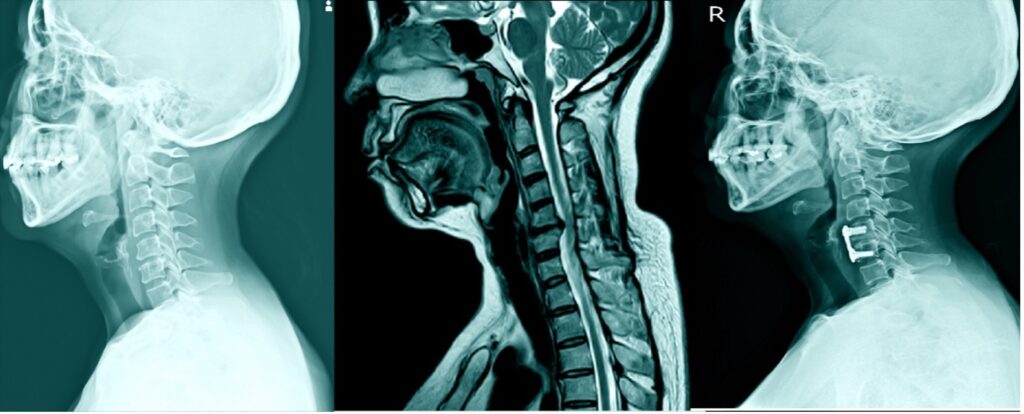

A cervical discectomy is a surgical procedure performed to remove a herniated or degenerated disc from the cervical spine (neck region). The procedure involves making an incision in the front(majority) or back of the neck and carefully removing the damaged disc to relieve pressure on the spinal cord or nerves. A small amount of bone may also be removed to access the damaged disc.

Cervical disc prolapse, also known as a herniated or slipped disc, is a condition that occurs when one of the discs between the cervical vertebrae in the neck slips out of its normal position and protrudes or bulges into the spinal canal. Spinal discs act as cushions between the vertebrae of the spine, enabling flexibility and movement of the spine.

This can cause pressure on the spinal cord or nerves, resulting in pain, weakness, numbness, or tingling sensations in the neck, shoulders, arms, and hands. The severity of the symptoms varies depending on the prolapse’s size and location, ranging from moderate to severe.